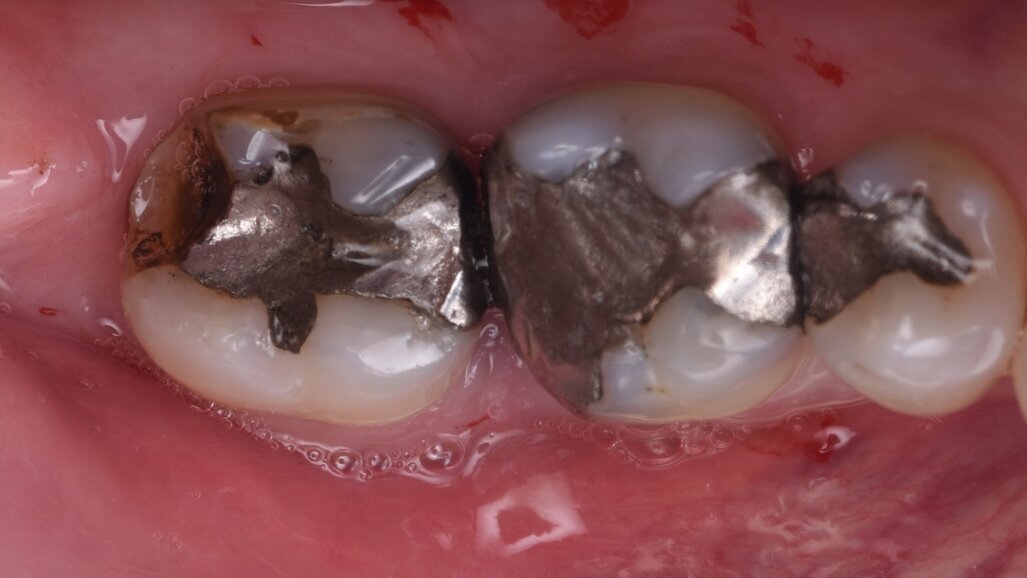

A 57-year-old male patient presented by referral with two failing molars, teeth #46 and 47. The patient had a clear medical history, and both molars exhibited extensive caries and restoration (Figs. 1–6).

The failing teeth were sectioned and extracted atraumatically to preserve the surrounding bone (Fig. 7). The sockets were thoroughly debrided using Lucas curettes to remove any residual infection or granulation tissue (Fig. 8).

The implants (5 × 9 mm CONELOG PROGRESSIVE-LINE, BioHorizons Camlog) were then placed using the sleeveless surgical guide and the CONELOG guided kit (Figs. 9 & 10).

After verification of the implant placement, the grafting material (MinerOss Putty allograft, BioHorizons Camlog) was packed into the site to the bone level to reduce the build-up of grafting material in the soft tissue.